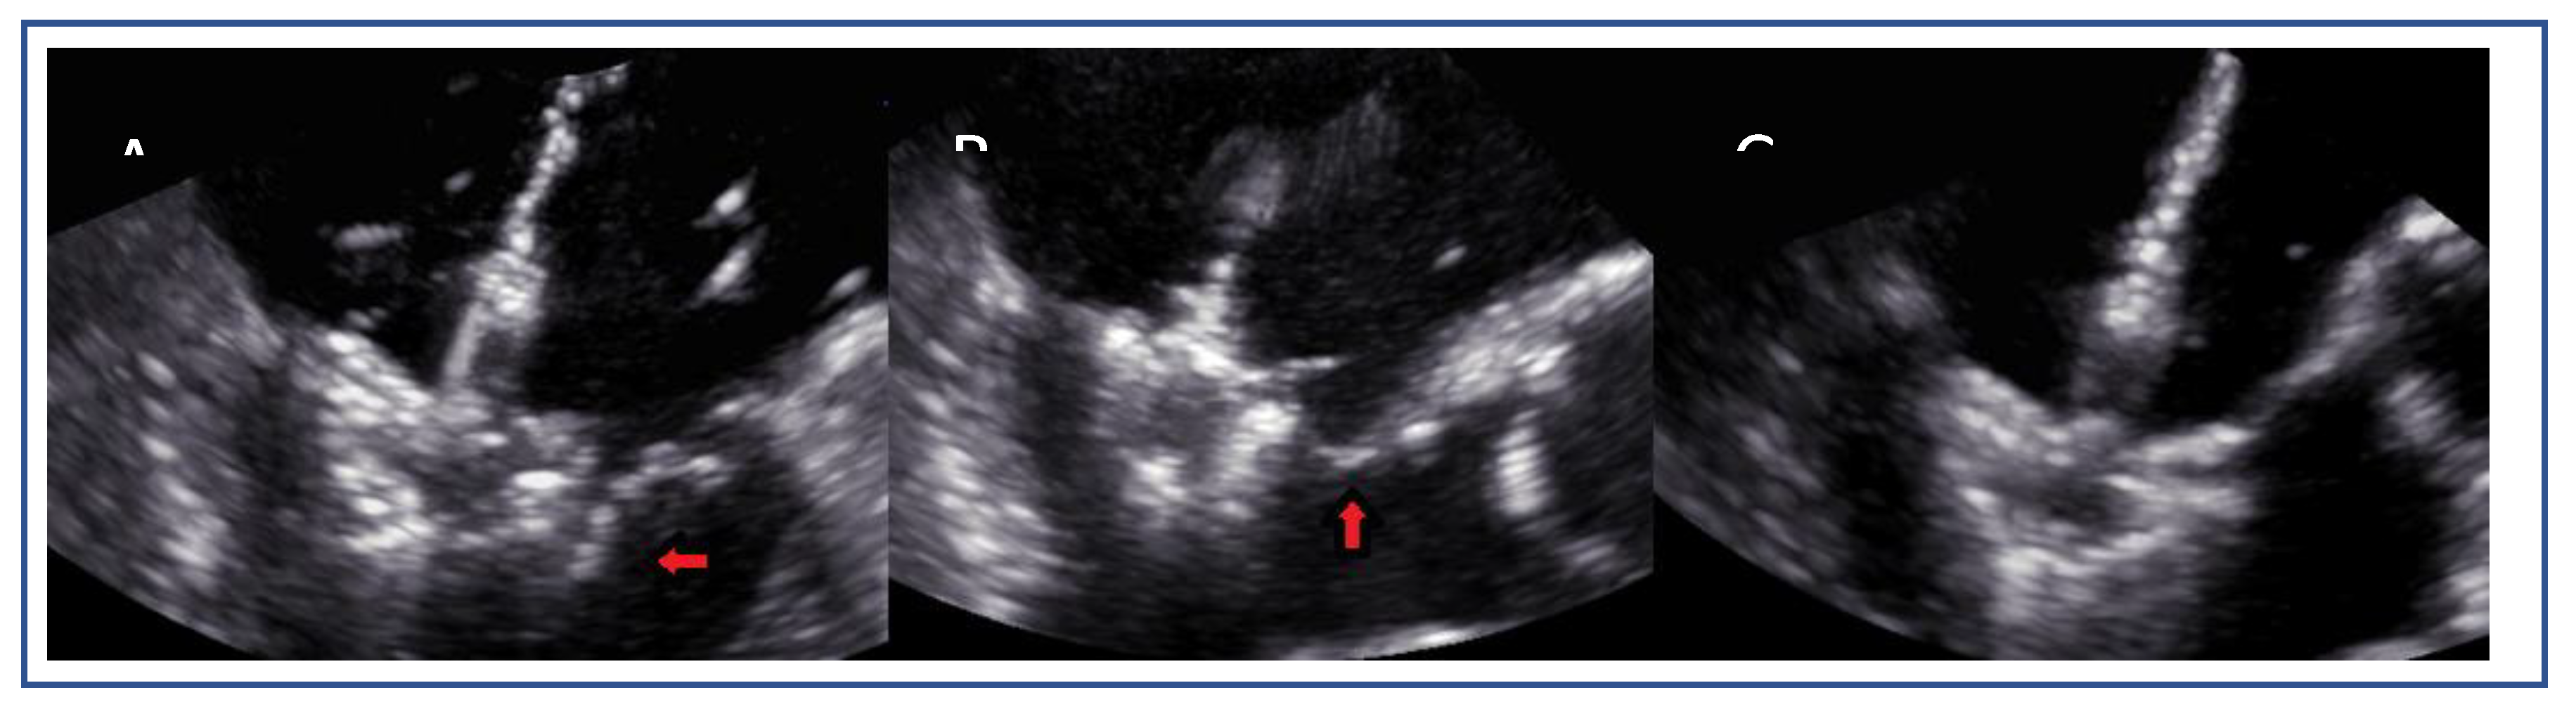

Posterior Leaflet Cleft-like IndentationThe posterior leaflet normally has two indentations that differentiate the scallops. A cleft-like indentation is defined as having a depth of at least 50% of the adjacent scallops [37,38] and 3D imaging is the best option to recognize such abnormalities (Figure 9). This feature makes grasping challenging and may lead to residual mitral regurgitation (MR).